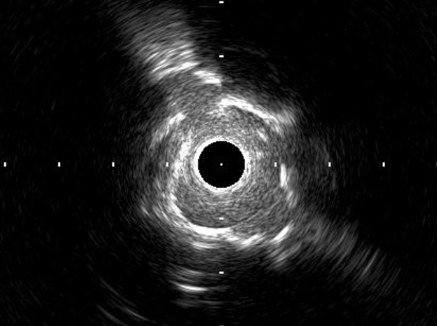

Rotational atherectomy with 1.25mm burr to LCxPoor expansion of NC balloon Further prepare lesion with shockwave 3.0.IVUS shows evidence of calcium fracture 3.0/15 stent deployed, followed by PSHP with NC 3.0 balloon Sion Blue redirected to LAD IVUS: concentric LM and pLAD calcification, 10 mm from mid LAD stent deployed 12 days ago

IVUS and angiogram show satisfactory stent expansion.